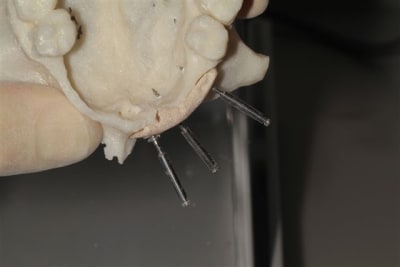

La première diapo est un essai pour justifier le concept (os non destiné à une utilisation greffe)

la deuxième est "tapée" dans une tête de femur de mauvais qualité (rejetée)

la troisième et suivante ce sont "les greffons" définitifs.

concept très prometteur. on obtient effectivement un contact intime du greffon avec le site receveur.